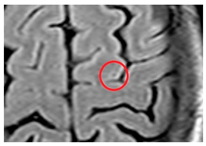

| Cortical cerebral microinfarct: | New additions with STRIVE-2 that are typically visible on microscopic neuropathological examination or high-field (7T) MRI. Some larger cortical cerebral microinfarcts (0.5–4 mm) can be seen on conventional MRI strength. | ![]() | <4 mm Hyperintense: T2, DWI (if acute) Hypointense: T1 |